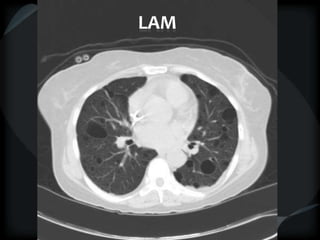

LAM

 Thin walled oval cysts

 Normal parenchyma

 Pleural effusion-chylous

 normal or hyperinflated lung

 angiomyolipoma